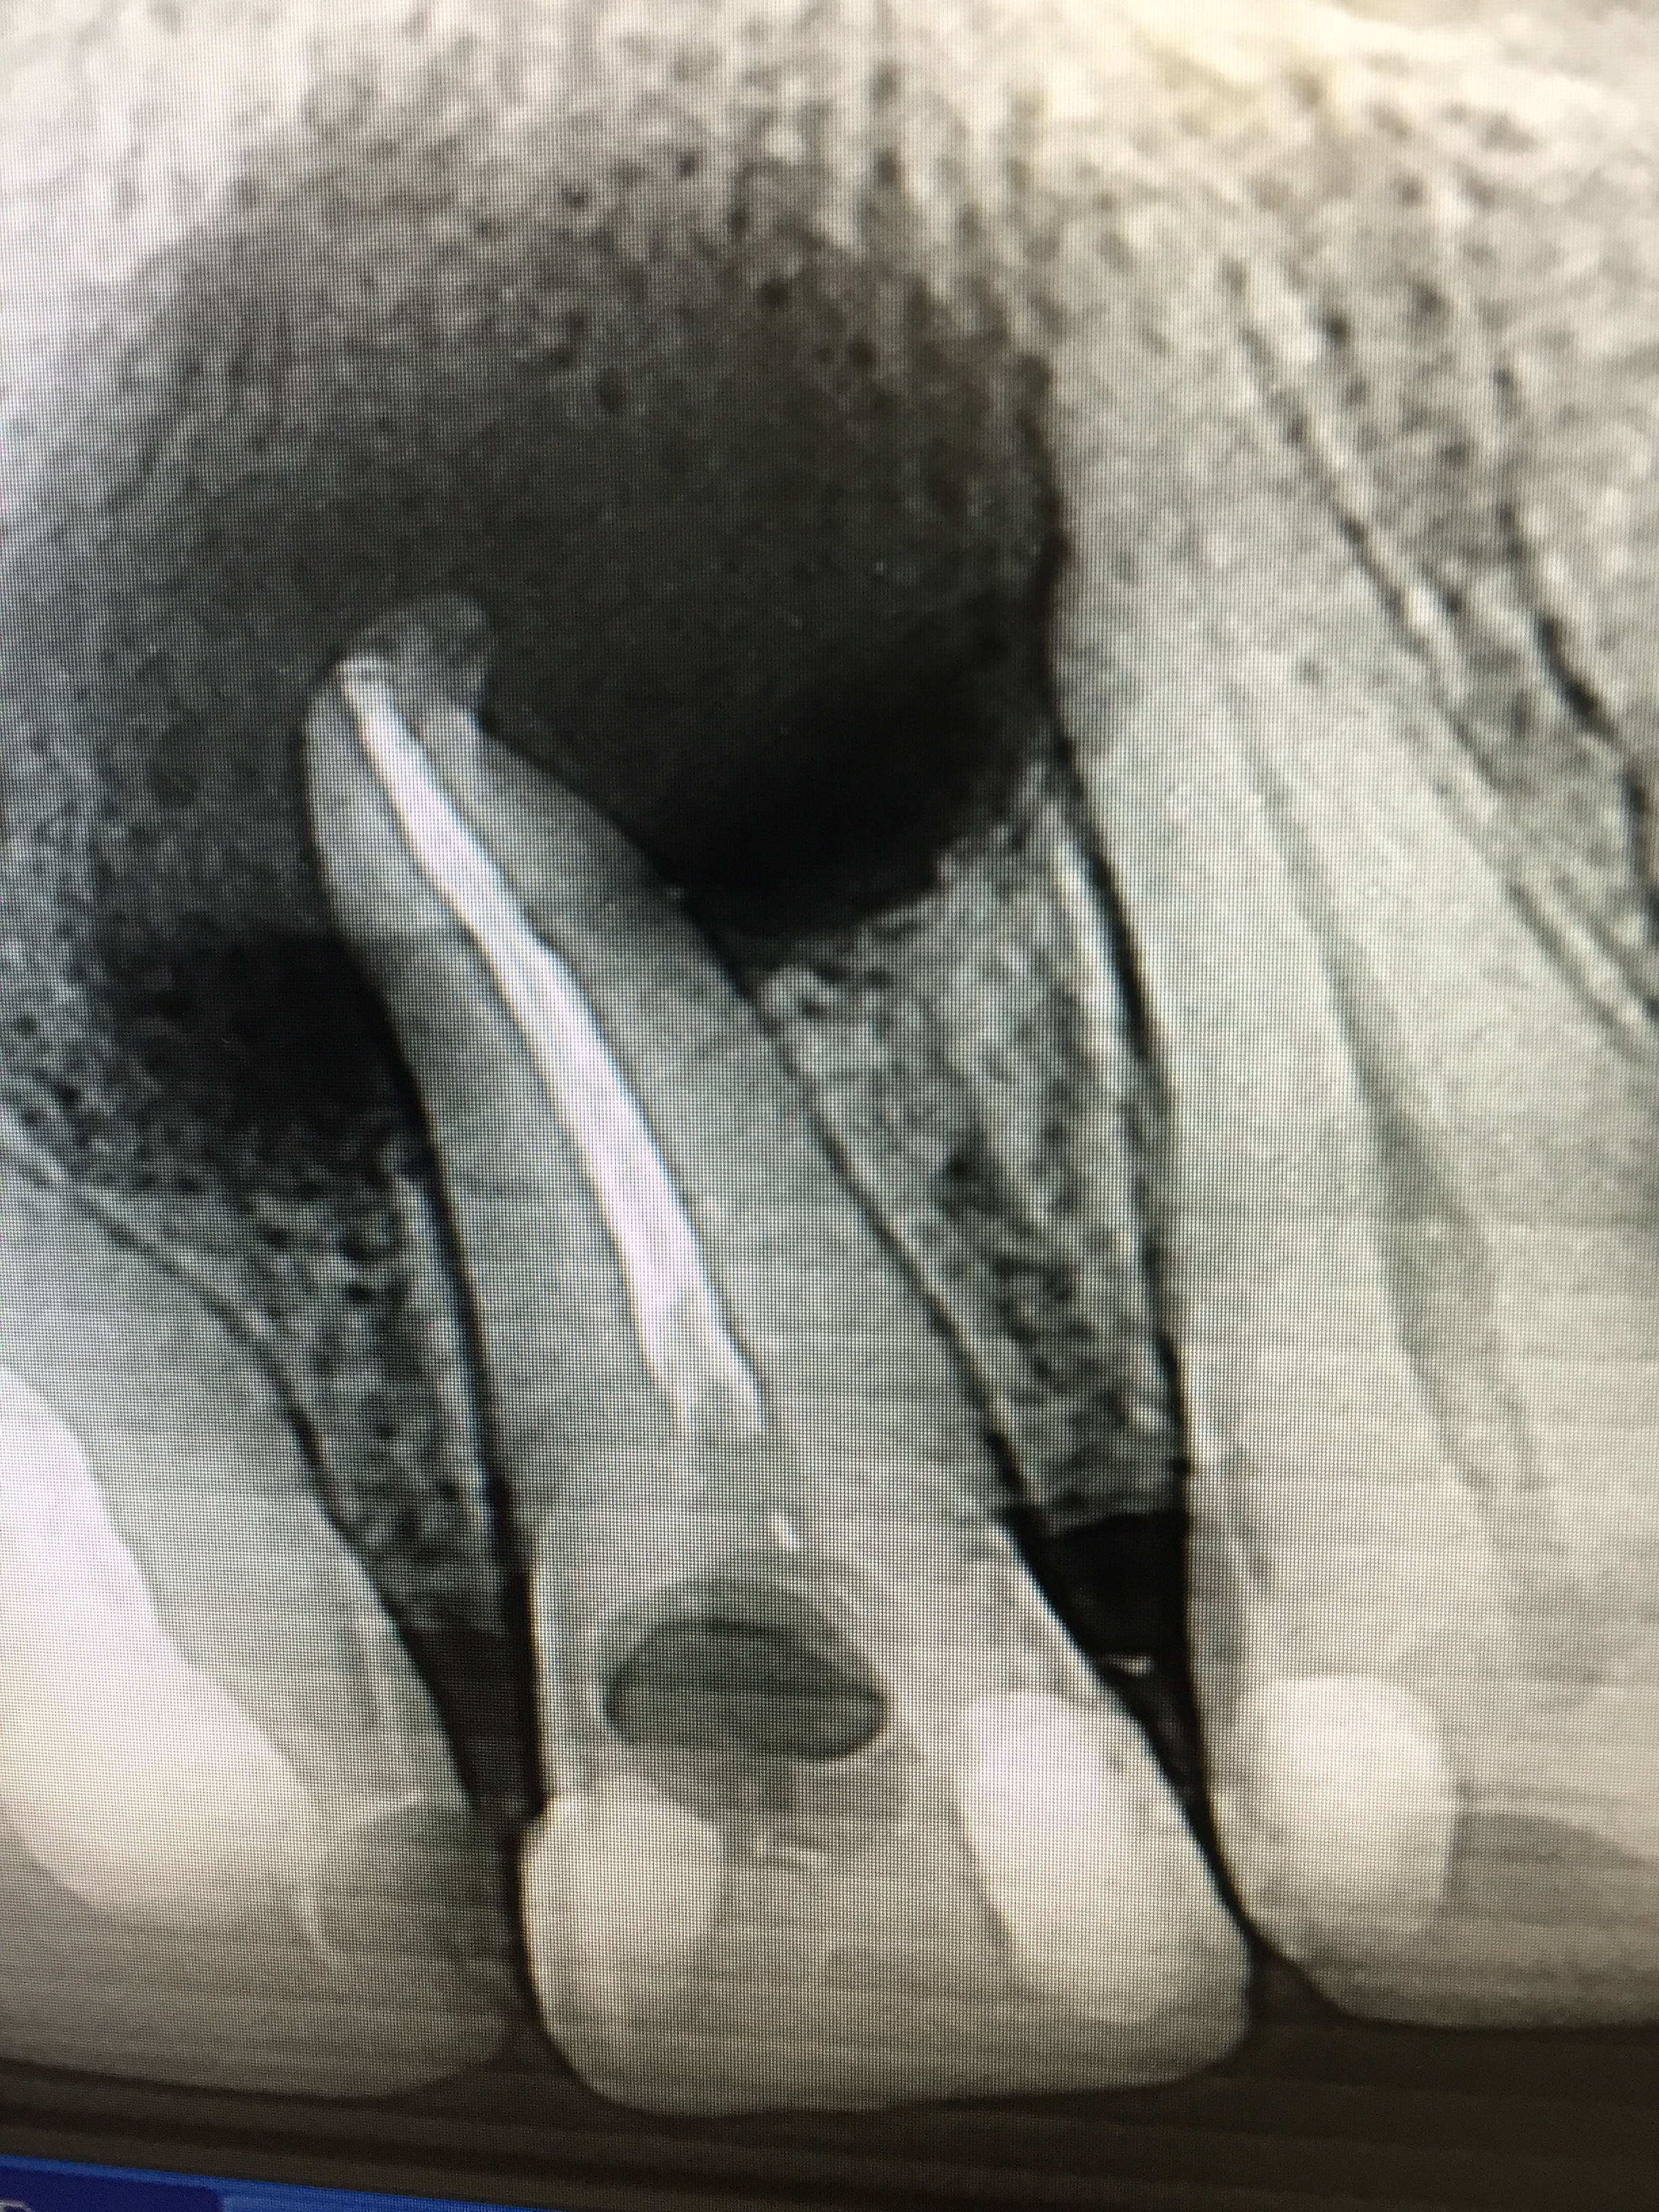

tu ne peux pas faire la RTE parcequ'il y a un apex deplace et l'indication d'une chir endo

D'accord avec lachmar, fracture du 1/3 apical : à extraire.

Aucun médecin ne connait mieux les dents ou la bouche qu'un chirurgien-dentiste. Nous seuls savons à quoi correspond réellement la lésion radio-claire visible à l'apex de cette dent : un bouillon de culture de stretptocoques et de germes anaérobies, entourés d'une zone très inflammatoire, aux nombreux capilaires dilatés dans lesquels se déversent à chaque minute plusieurs milliers de bactéries.